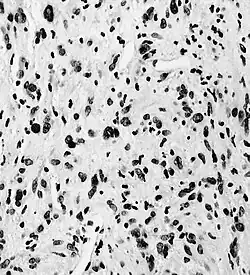

boven gezonde hersenen, onder met astrocytomen

Een astrocytoom is een hersentumor die is ontstaan uit astrocyten, stervormige cellen die als het ware het dragend weefsel van de hersenen vormen. Astrocytomen zijn kwaadaardige tumoren.